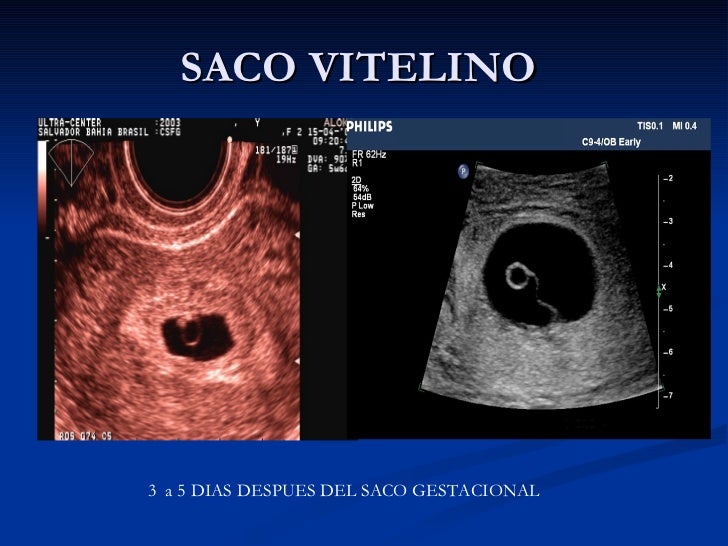

El saco vitelino es una estructura circular con una pared hiperecoica y mide aproximadamente 3-5 mm. Sin embargo, la pérdida temprana del embarazo es el término que se utilizará en este Boletín de práctica. El saco vitelino secundario es la marca embrionaria más temprana visualizada por ecografía; por lo general se identifica alrededor.

El saco vitelino es la primera estructura que puede identificarse en el interior del saco gestacional. Se identifica como una estructura quística redondeada, de pared fina, dentro del saco cuando este alcanza los 6-8 mm, a partir de las 3,5 semanas de embarazo.

A través de eco vaginal se visualiza ya sobre las 5 semanas. Su diámetro aumenta de 2 a 9 mm entre la semana 5 y la semana 11. El saco vitelino está adosado al embrión y le suministra nutrientes y también oxigeno, en los humanos el saco vitelino funciona como un sistema circulatorio primario antes que comience la circulación interna. El.